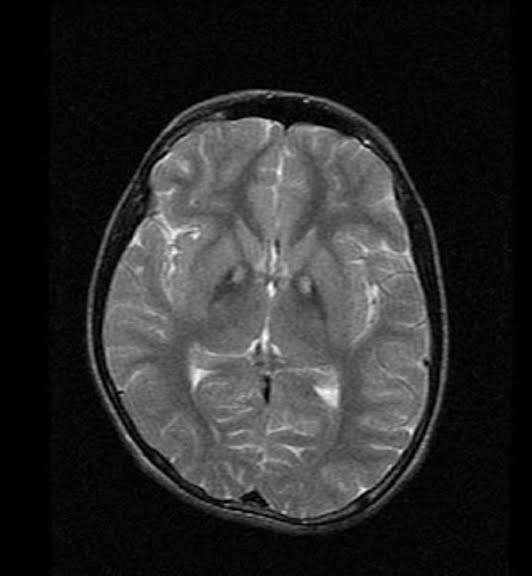

Hellervorden Spatz Disease Symptoms

What are the symptoms of Hallervorden-Spatz disease? rigid muscles. writhing movements. tremors. seizures. confusion. disorientation. stupor. dementia.